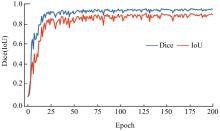

针对脑皮层下组织部分结构(如纹状体)在医学影像中目标小、对比度低,图像分割难度大,在自动医学诊断中应用比较困难的问题,本文基于深度学习的方法提出了一种医学图像分割网络,在磁共振成像中分割组成纹状体的苍白球、尾状核、壳核3部分。本文提出的网络模型具有捕获全局和局部特征的能力,并建立了全局与局部信息的相关性,在深度不退化的同时有效融合不同尺度的深层语义特征和浅层细节特征,实现对纹状体的精确分割。模型在公开的脑部数据集上进行了验证,并与其他先进的方法进行对比,结果表明本文的戴斯相似系数、平均交并比、95%豪斯多夫距离分别为94.26%、90.94%、3.82,均优于其他几种方法,达到了先进水平,这表明本文模型可以提高对纹状体的分割精度,为相关疾病的研究提供依据。